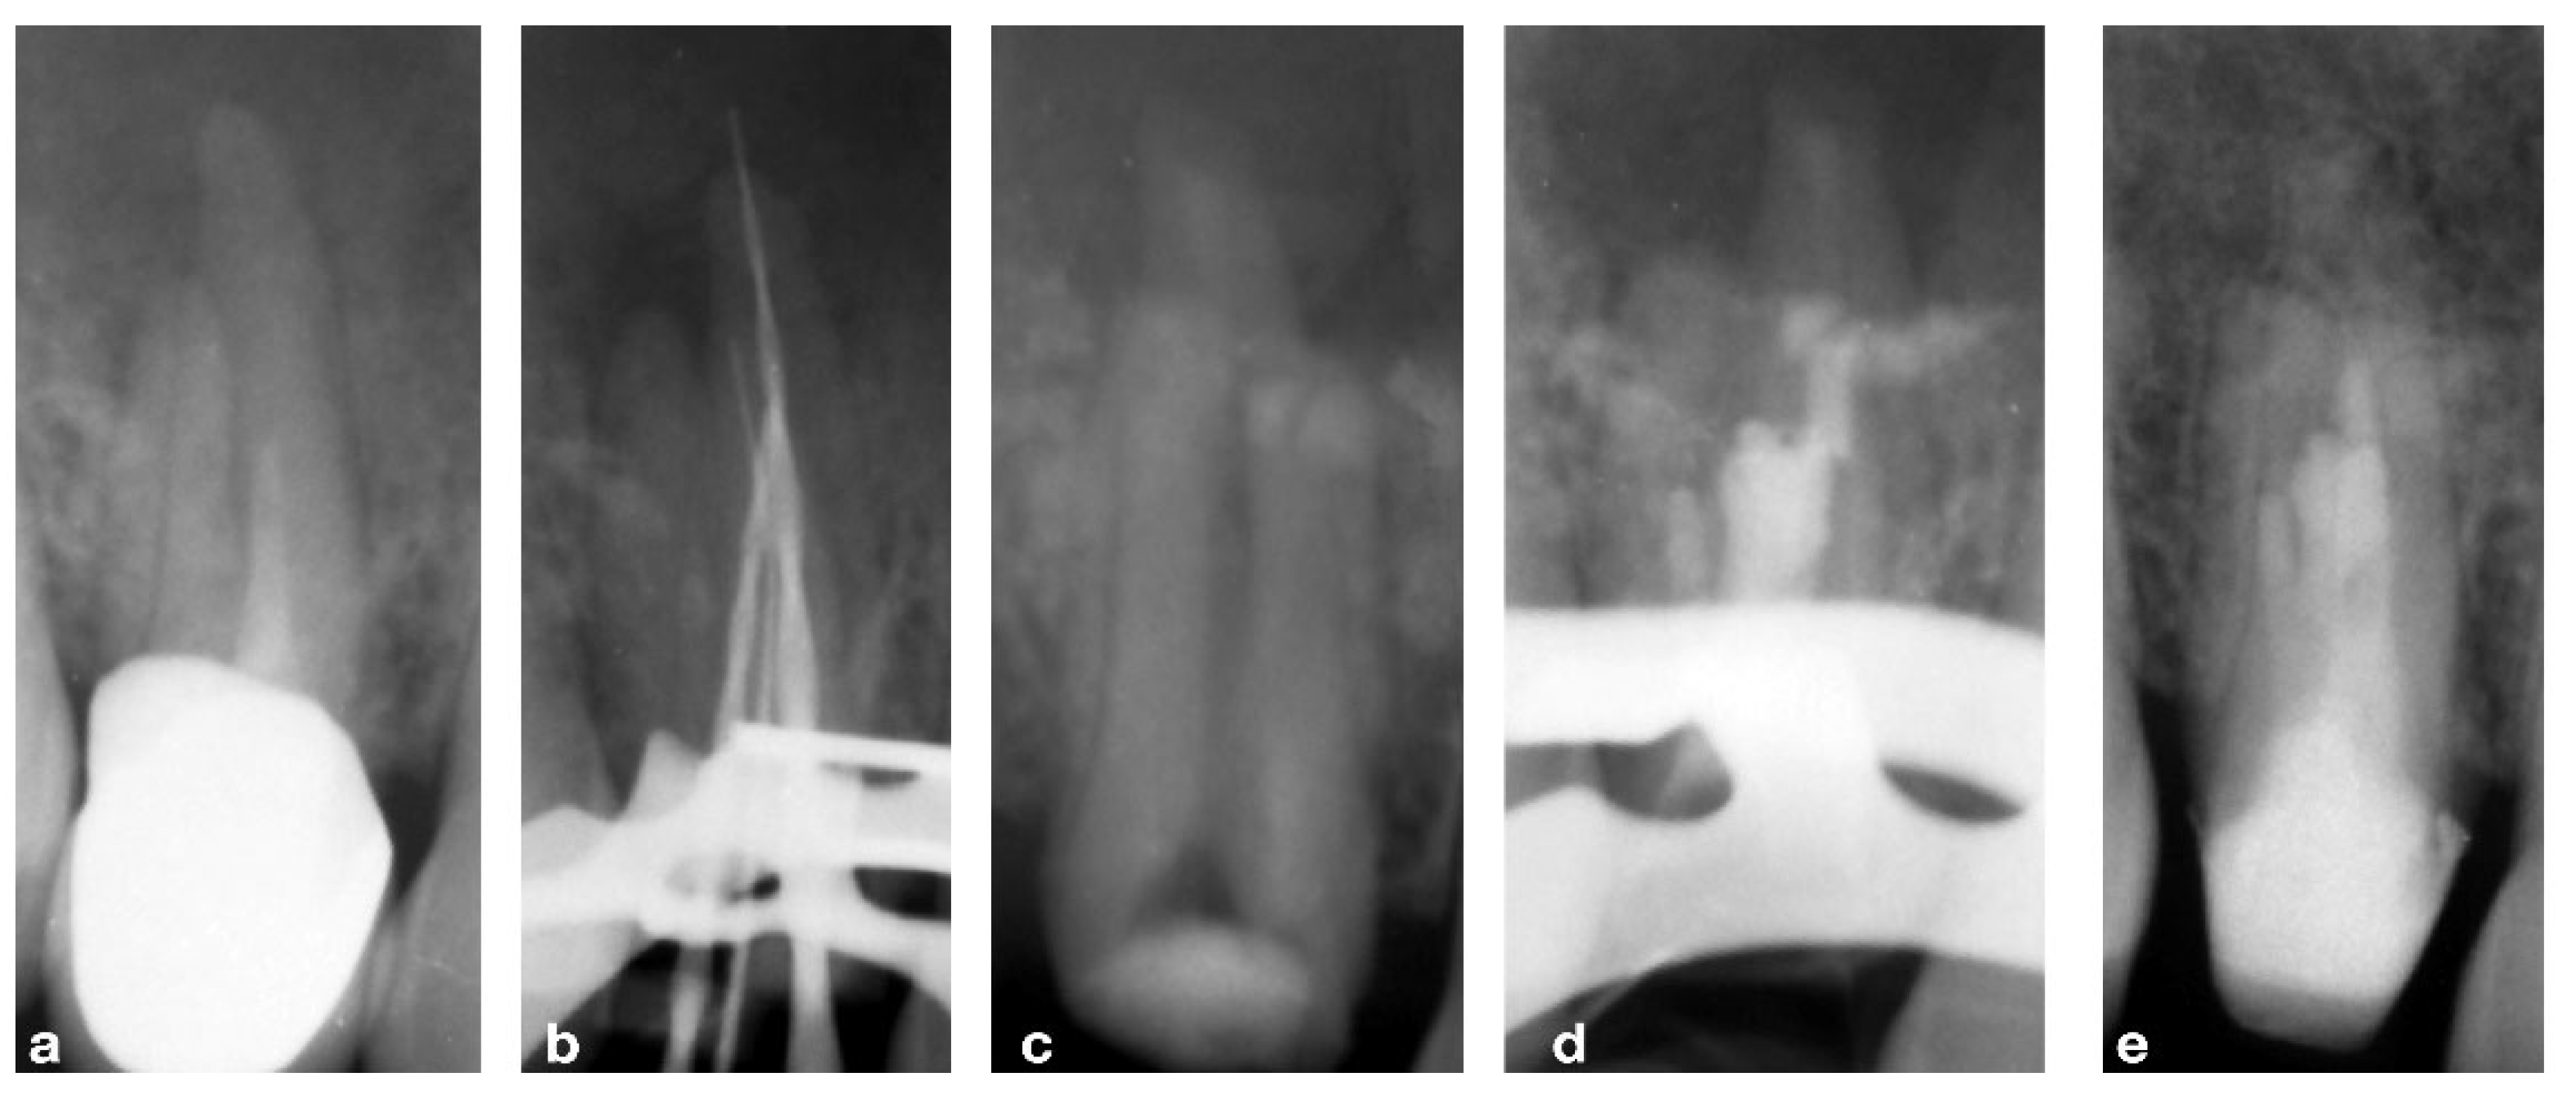

2.2. CASE 2